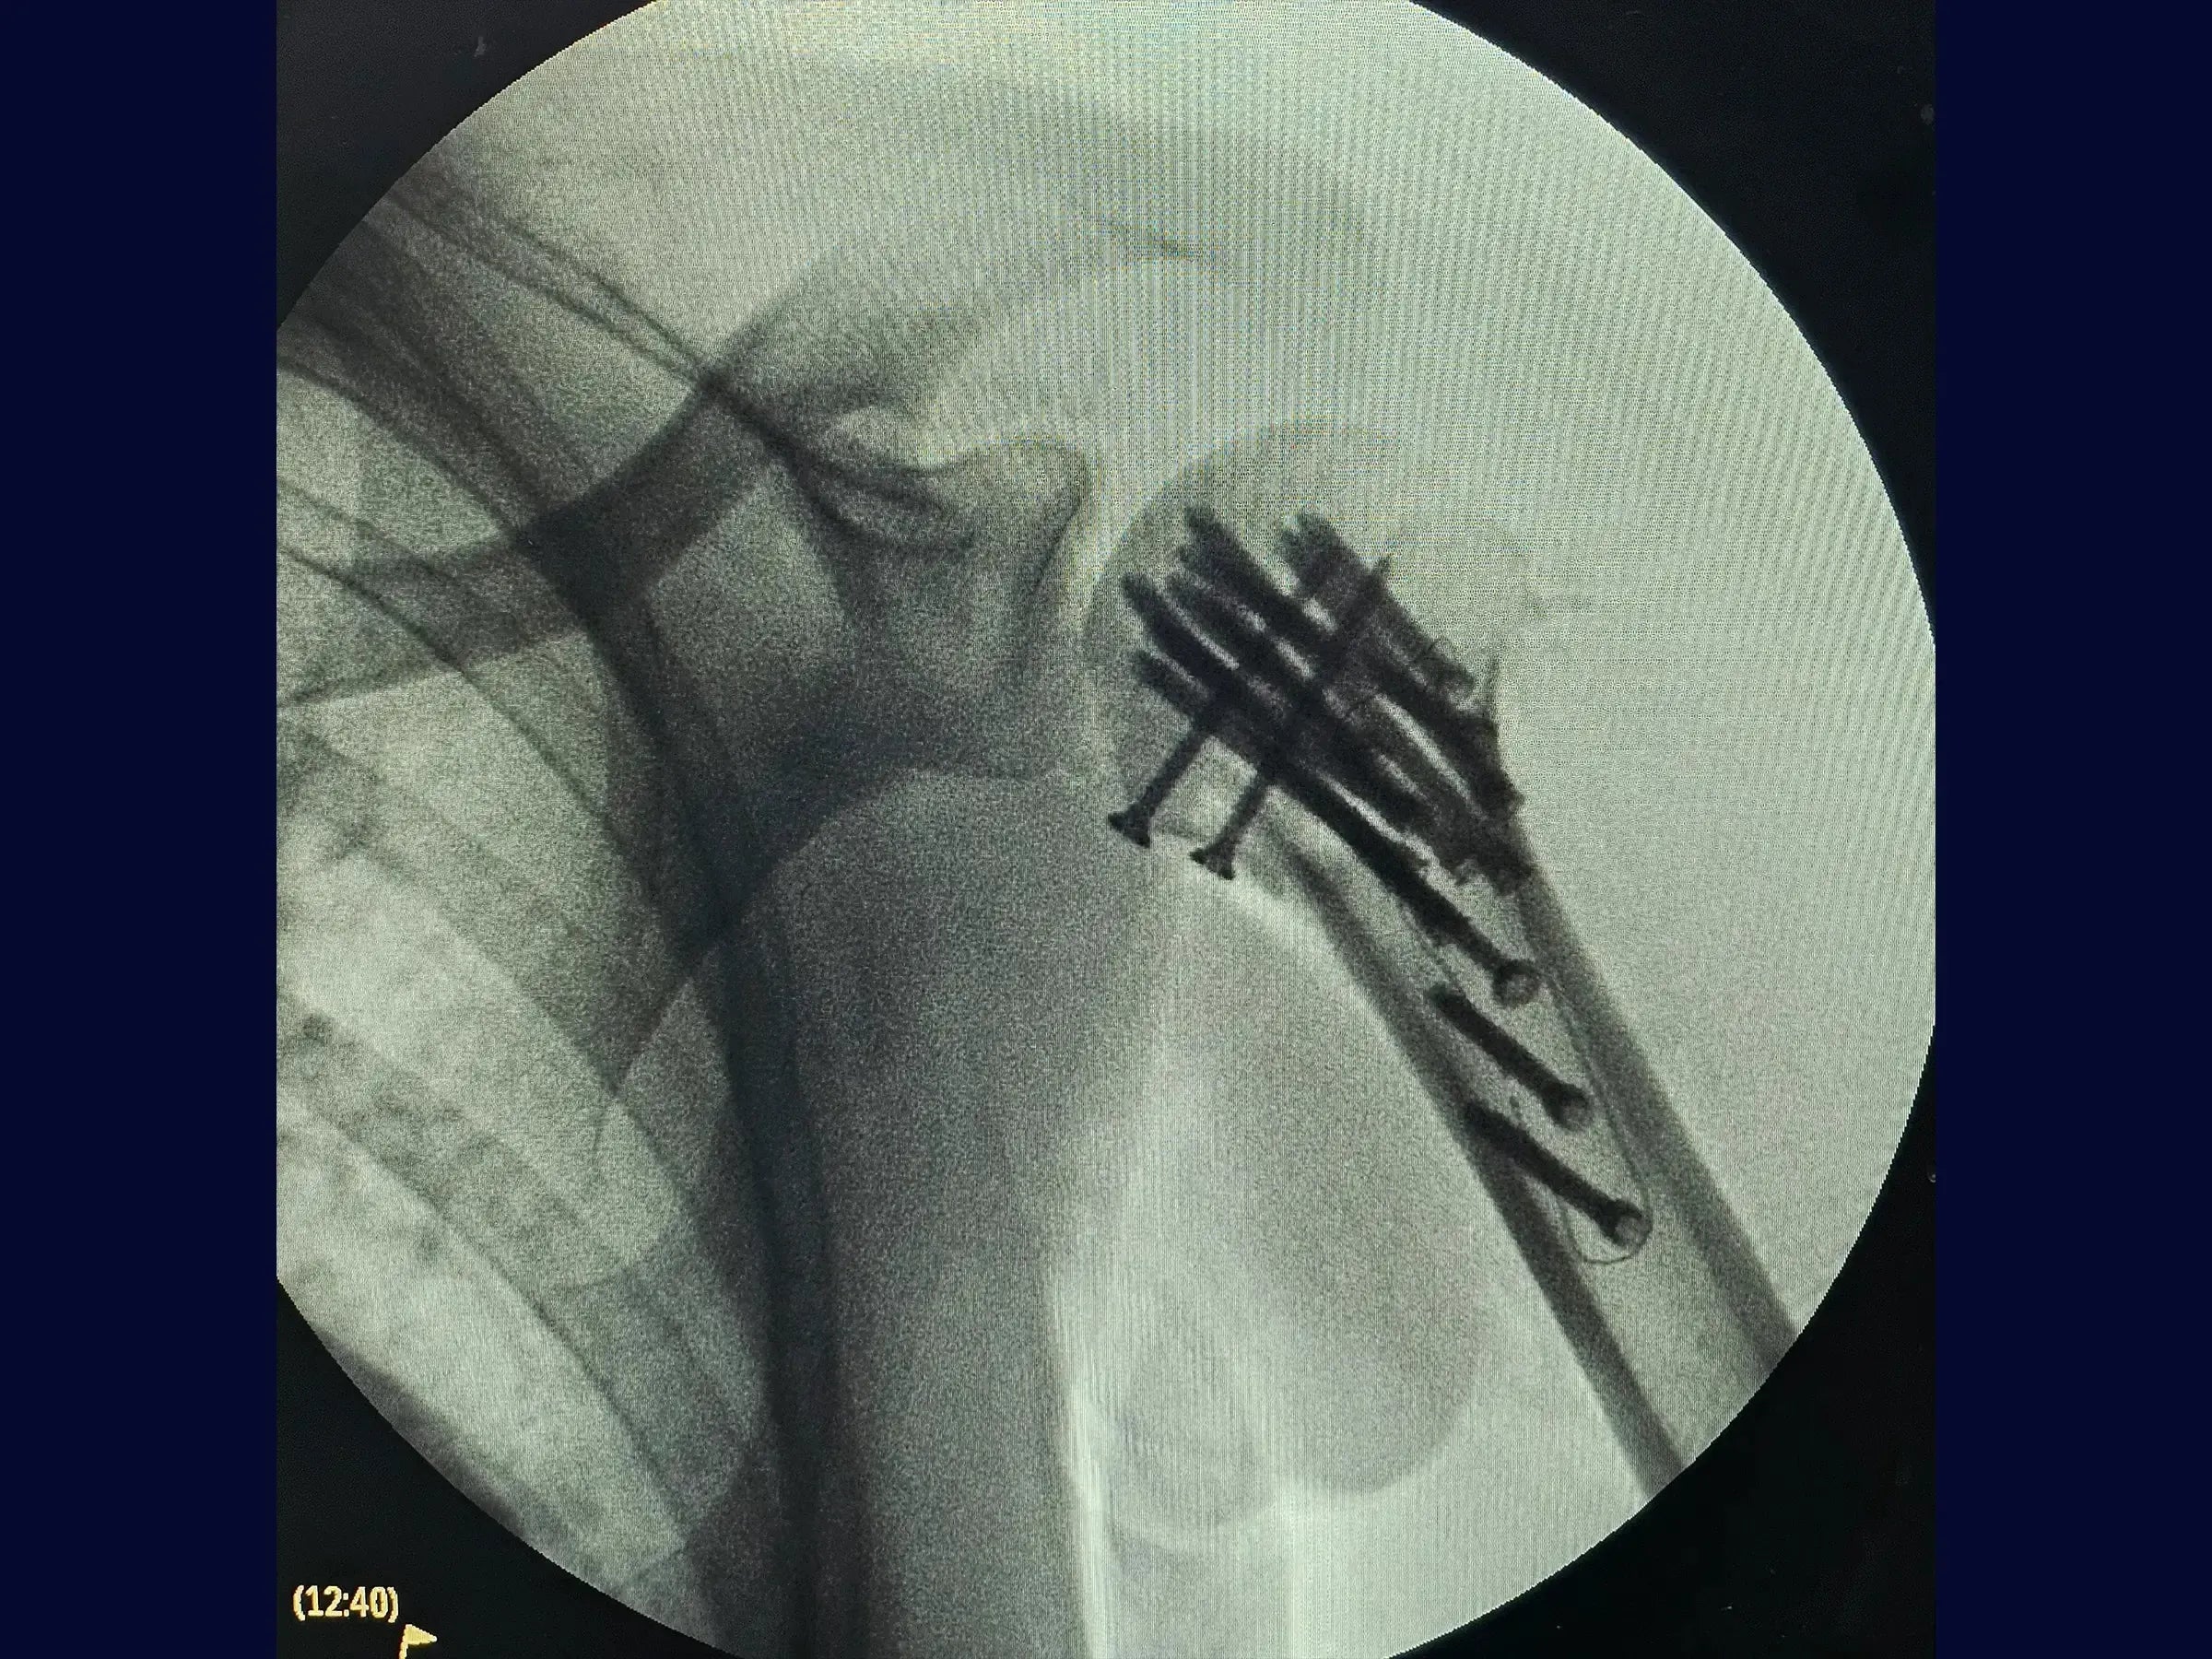

- Fixação com placa de fibra de carbono e parafusos para estabilização de fragmentos.

- Fixação com Placa de Fibra de Carbono: Procedimentos para a amarração do manguito rotador e estabilização da articulação, mesmo diante de fragmentos soltos.

- Manejo de Fragmento da Pequena Tuberosidade: Abordagem para fixação isolada de fragmentos soltos, como a pequena tuberosidade, utilizando parafusos adicionais.

- Posicionamento Anatômico Otimizado: Técnicas para garantir a redução da articulação com posicionamento anatômico e tuberosidades amarradas para um resultado seguro.